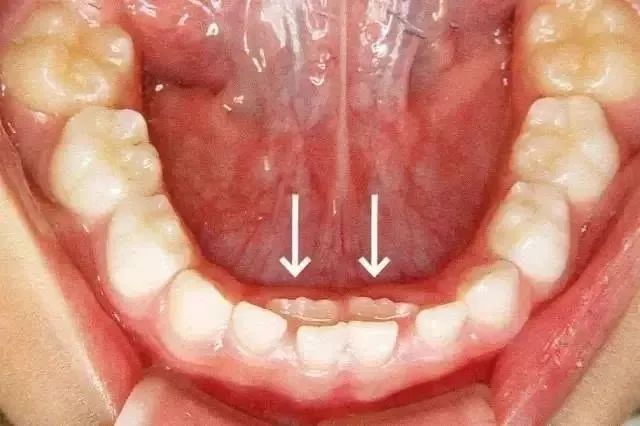

小朋友呢個係乳牙還冇脫落,新牙就長出嚟了,表現係”雙排牙“現象。呢種情況就係我地所講嘅“乳牙滯留”。

箭頭所指係恆牙